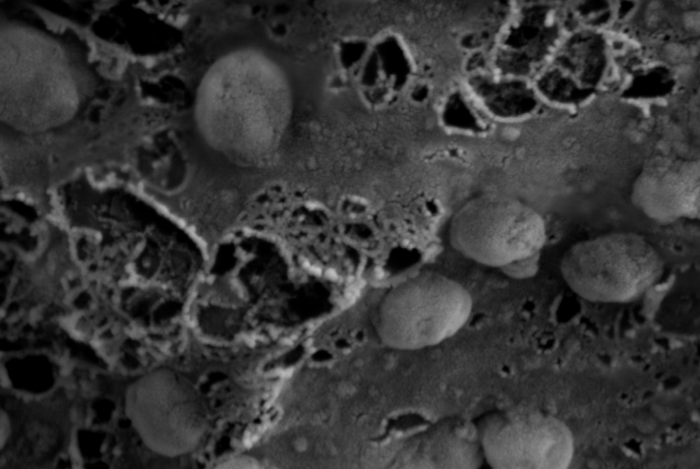

Their research demonstrates that scientists could engineer nanosized parts of cells called exosomes to carry therapeutic cargo to hard-to-reach places, including the nearly impenetrable blood-brain barrier. This innovative delivery system paves the way for a future where it’s conceivable that engineered exosomes could carry cargo that either suppress infectious diseases or restructure genetic material so that pathogens are rendered harmless.

“The ZPAMt HIV protein repressor we developed is packaged into exosome nanoparticles and can enter cells where it epigenetically silences HIV,” Morris said. “We show that these nanoparticles can systemically ‘block and lock’ HIV expression. This is the first time that block and lock has been successfully delivered to treat HIV in vivo in the brain.”